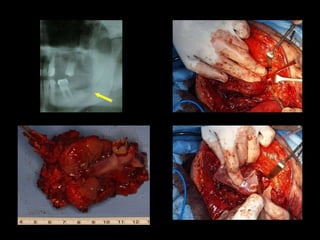

Mejor planificación estética Y funcional mandibular en el auto trasplante de tejidos. Disminución del tiempo quirúrgico en el modelado de la placa mandibular 60´. Mantenimiento de la relación céntrica. Mayor exactitud con la “técnica en espejo”.

Evitar contaminación de campos. Mayor eficiencia al planificar y realizar las osteotomías mandibulares. Mayor eficiencia al planificar y realizar las osteotomías del peroné.

La oncología es una de nuestros mayores retos dentro de nuestra especialidad donde la cirugía ablativa y la cirugía reconstructiva se enfrentan. Cirugías de alto coste: para el paciente, el equipo quirúrgico, el hospital y el sistema sanitario. El acceso a biomodelos nos permitió la exploración de su uso y su utilidad.